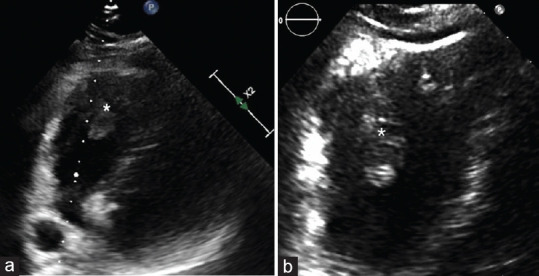

Heart metastatic tumors are more frequent than primary heart tumors. Cardiac metastasis is a rare phenomenon, occurring mainly by direct spread, especially from lung cancer. Cardiac metastases may be asymptomatic or cause arrhythmias, nonspecific electrocardiographic alterations, or mimic a myocardial infarction. In this case report, we illustrate a rare case of pulmonary adenocarcinoma, which through the bloodstream developed a stalactite-shaped metastasis within the right ventricle of conspicuous size (20 mm × 34 mm × 12 mm). In addition, the tumor compressed the right pulmonary trunk, causing pulmonary hypertension. It is essential to characterize metastasis with multimodality imaging. Such lesions within the right cavities can cause massive pulmonary embolism, as in our case, leading to the patient's death, thrombolytic therapy not being effective.